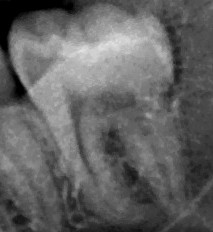

This is an example of an image used to train our model. The model has been trained with data from 12 countries and 4 continents so it can generalize to data from never seen samples. It gets a mean absolute error of 1.07 years and an accuracy of 88.38% (for the 18 years threshold) in test. Regarding never seen samples, it gets a mean absolute error of 1.21, 1.45, 1.36 and 1.51 years and an accuracy of 92.04, 81.97, 85.03 and 86.08% in four samples from Russia, Ethiopia, Egypt and Australia, respectively.